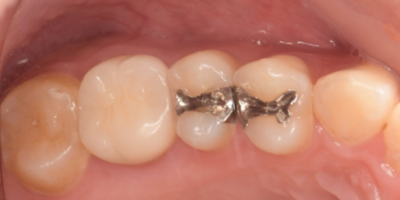

移植3ヶ月後の口腔内写真

移植3ヶ月後。

歯根周囲に透過像を認めるが動揺などはなく、歯周ポケットも形成されていなかった。